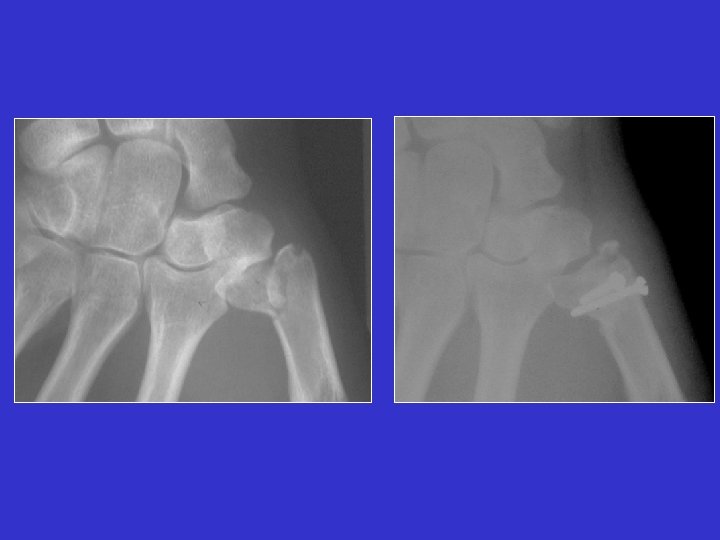

Fractura de Benett

Tratamiento de la fractura de Benett Reducción ortopédica y yeso

Fractura del 1 er metacarpiano

Enclavijado carpo-metacarpiano Enclavijado inter-metacarpiano

Fracturas de la base (Rolando)

Luxación Carpo-metacarpiana fotos J. Chouteau